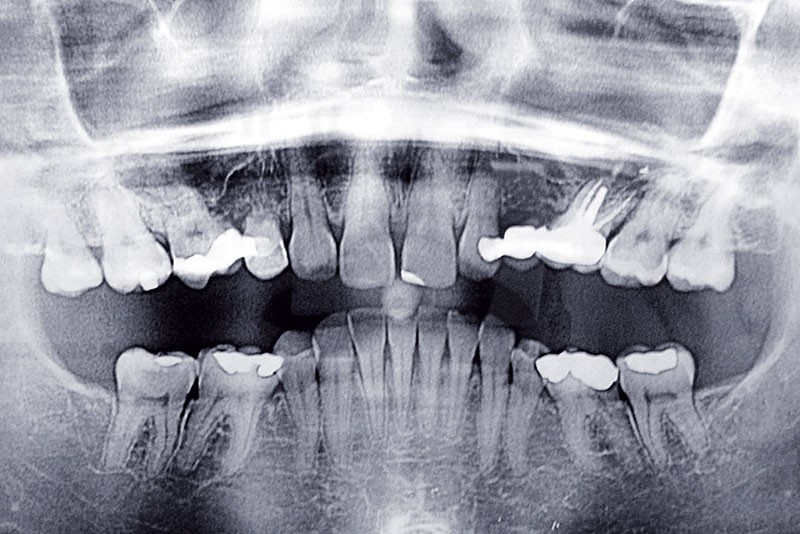

La patiente, âgée de 30 ans, présente des agénésies multiples : 12, 22, 14, 15, 24, 25, 35 et 45 (fig. 1 à 3).

Malocclusion de classe II par rétrognathie mandibulaire dans un schéma squelettique hypodivergent (fig. 4 à 6).

On note une forte supraclusion incisive (fig. 7 à 9).